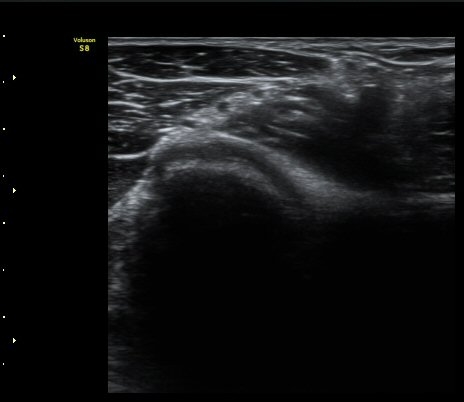

ÃÊÀ½ÆÄ °Ë»ç